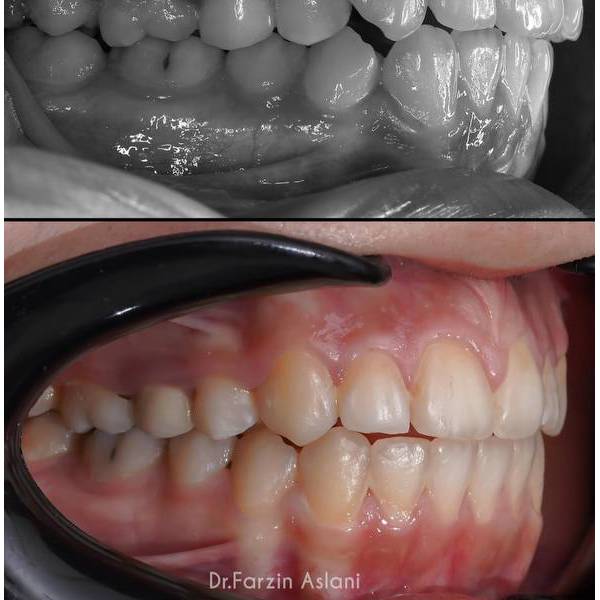

نمونه کار متخصص ارتودنسی تهران

در بخش زیر نمونه کار قبل و بعد ارتودنسی توسط دکتر فرزین اصلانی را مشاهده می کنید :